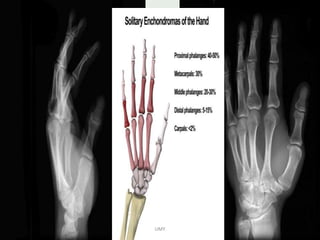

- Radiographic features : metaphysis of immature

skeleton ,

DIGNOSTIC- well marginated , centrally located ,purely

lytic lesion.

radiolucent that expand and thin the cortex .

FALLEN FRAGMENT SIGN - # fragment in the cyst

DD : ABC & fibrous dysplasia